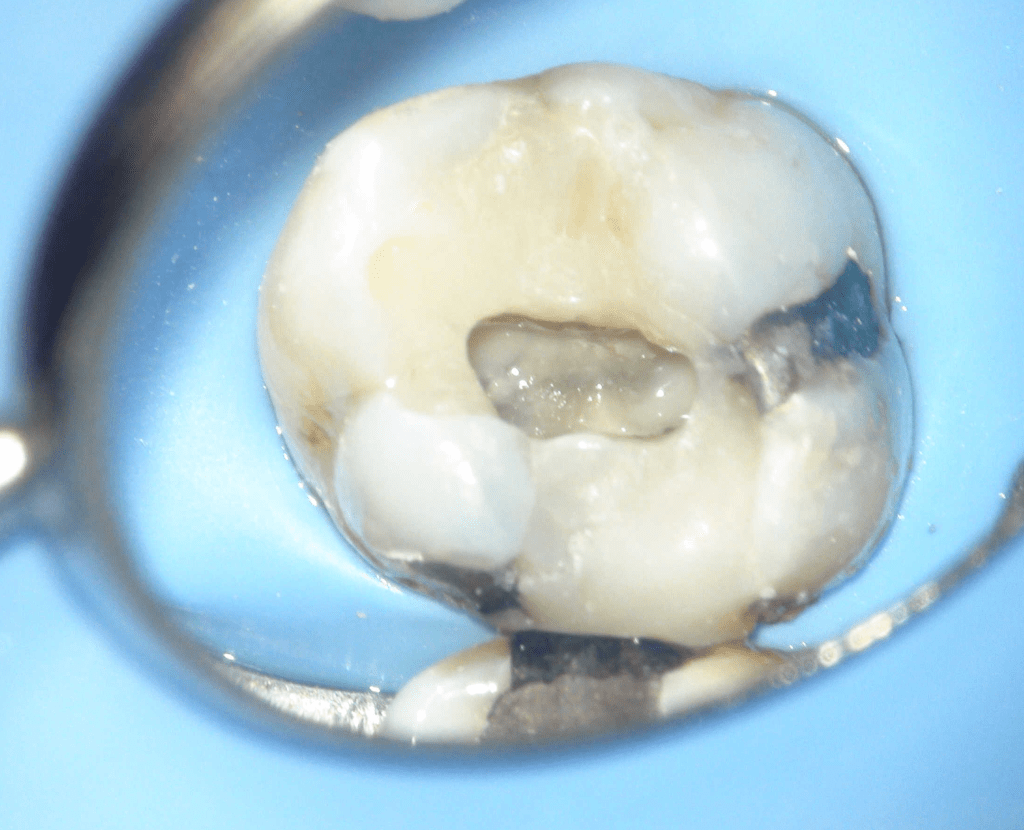

Fisura, remoción amalgama para explorar